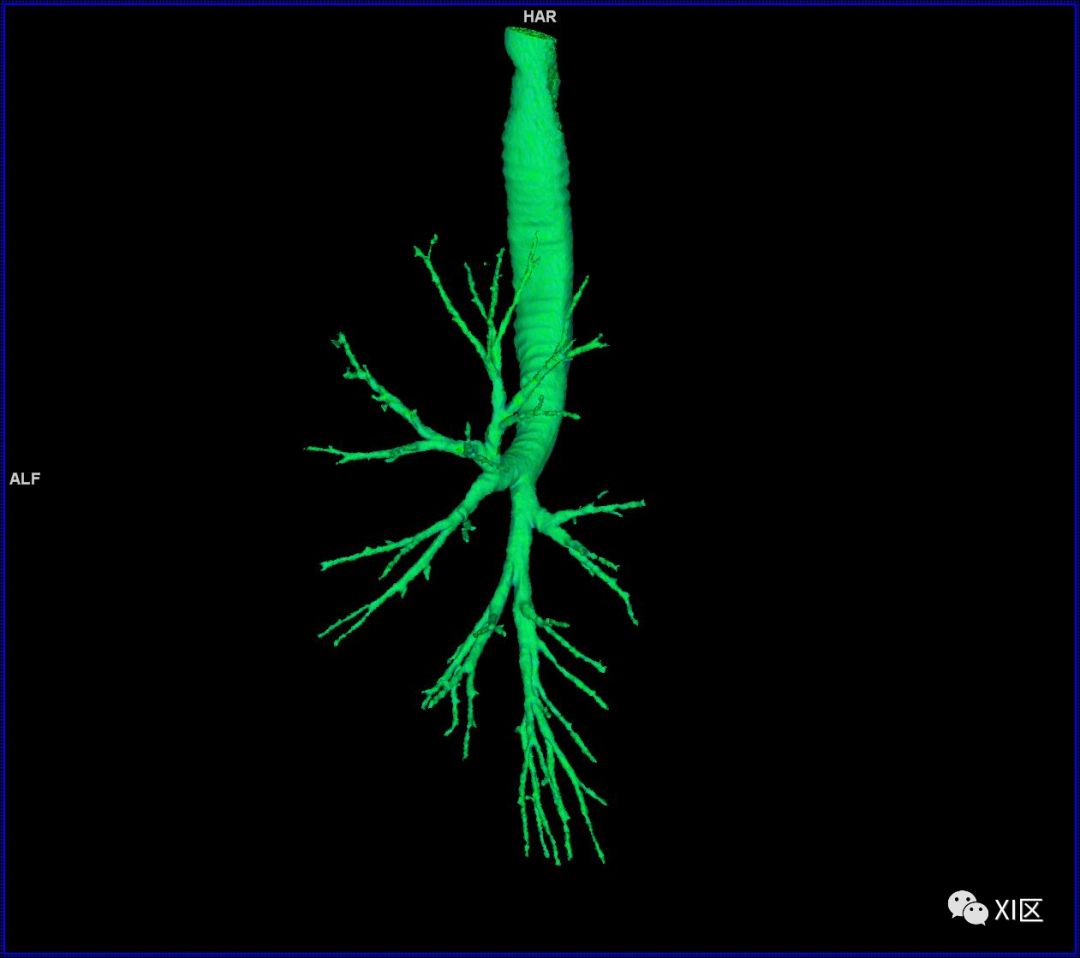

气管支气管树与两肺融合显示

气管树的解剖

人的支气管(第1级)至肺泡约有24级分支。支气管经肺门入肺,分为叶支气管(第2级),右肺3支,左肺2支。叶支气管分为段支气管(第3~4级),左肺8支、右肺10支。段支气管就是肺的分段的依据。段支气管反复分支为小支气管(第5~10级),继而再分支为细支气管(第11~13级),细支气管又分支为终末细支气管(第14~16级)。从叶支气管至终末细支气管为肺内的导气部。终末细支气管以下的分支为肺的呼吸部,包括呼吸细支气管(第17~19级)、肺泡管(第20~22级)、肺泡囊(第23级)和肺泡(第24级)。

气管支气管形如树状,因此也称气管支气管树。

气管树